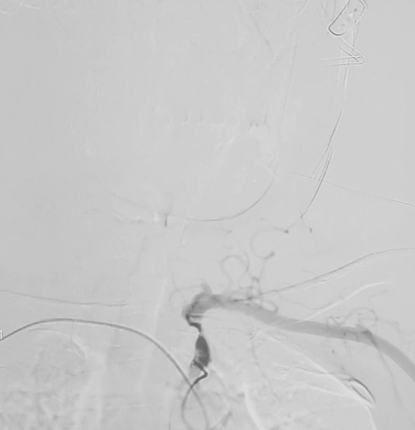

支架释放,一锤定音:

wuwei